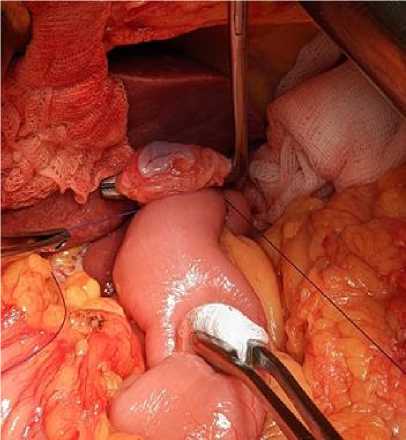

Завершающим этапом является инвагинация области анастомоза с использованием серозно-мышечных П-образных (салазочных) швов. Первый стежок накладывается на серозную оболочку тонкой кишки параллельно ее продольной оси, второй – перпендикулярно оси пищевода, а третий – снова параллельно оси тонкой кишки. Последовательное затяги- вание швов приводит к инвагинации области анастомоза (рис. 7). В случае затруднений при затягивании швов и недостаточной инвагинации рекомендуется аккуратное мануальное давление на область анастомоза для облегчения ее погружения под П-образный шов. После проверки на герметичность назоинтестинальный зонд удаляется.

Рис. 7. Последовательное затягивание швов, инвагинация зоны анастомоза

Fig. 7. Sequential suture tightening and anastomosis invagination